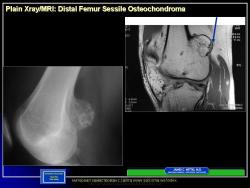

Иллюстрации из литературных источников.

14.N.Slayd15.JPG15.N.Slayd16.JPG16.N.Slayd17.JPG17.N.Slayd18.JPG18.N.Slayd19.JPG19.N.Slayd20.JPG1.1.Slayd20.JPG2.2.Slayd21.JPG3.3.Slayd22.JPG210.OH_.Slayd25.JPG